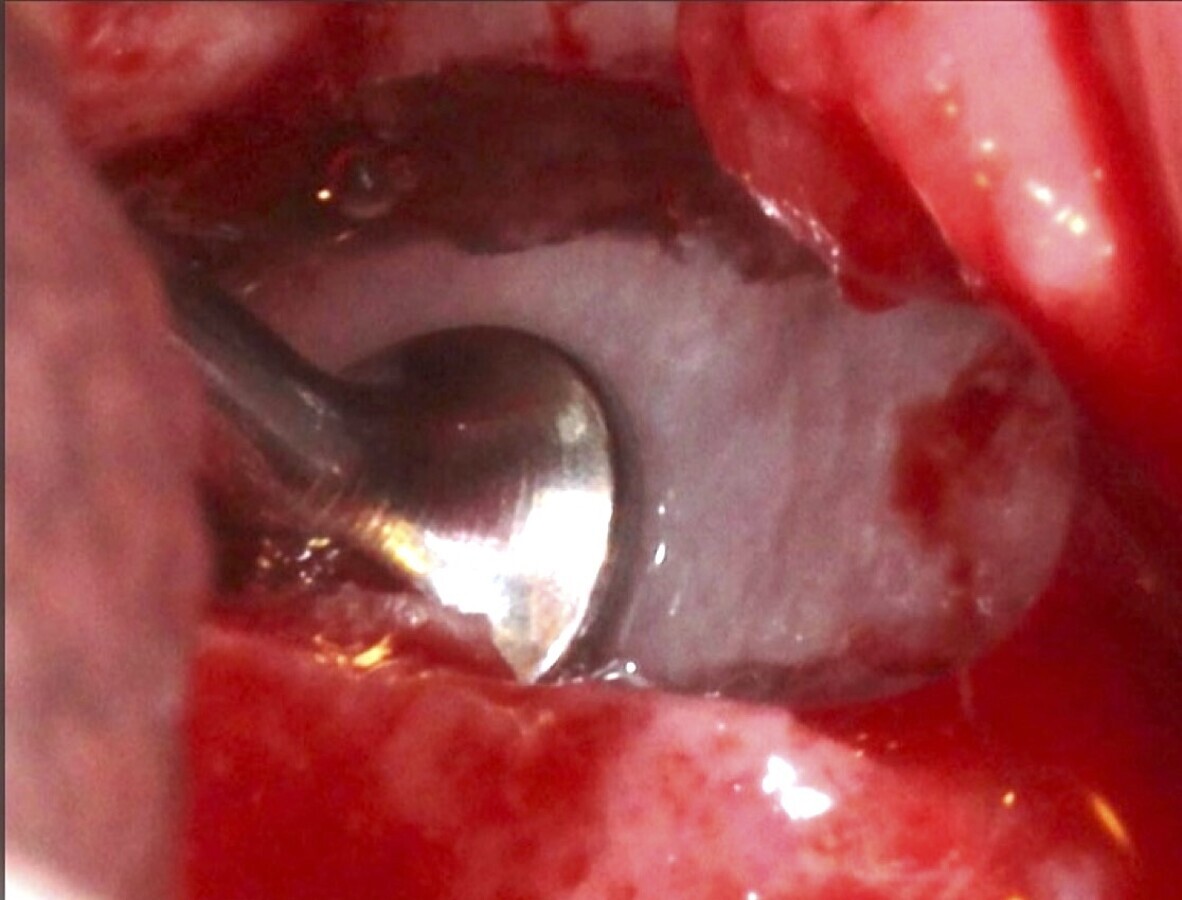

Se inicia la elevación de la membrana de Schneider con el inserto redondeado no cortante en forma de disco, empleando movimientos suaves. El levantamiento puede complementarse con elevadores convencionales, siguiendo la dirección mesiodistal. La fase de desprendimiento inicia con el piso y sigue hacia la pared mesial para terminar, y de ser necesario, hacia la pared posterior. Existen diversos insertos con angulaciones y longitudes para mayor accesibilidad16 (Figura 1).

Figura 7. Inserto de presión hidráulica iniciando el desprendimiento de la membrana de Schneider (a, b ).

Figura 17. Inicio del desprendimiento de la membrana de Schneider con el inserto de presión hidráulica.